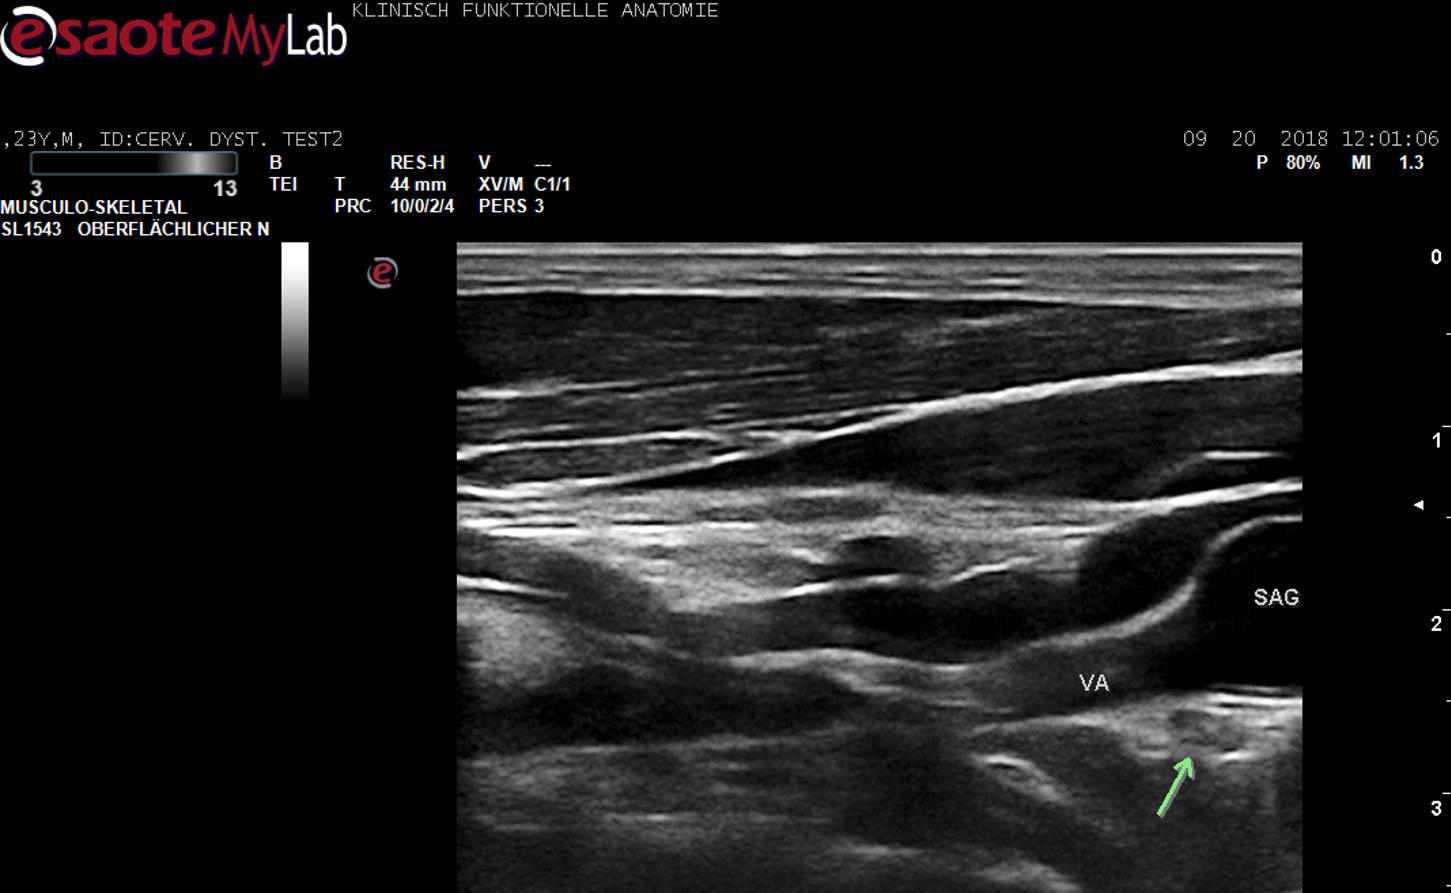

Weltweit erste US-Darstellung des Ganglion stellatum (grüner Pfeil) in unmittelbarer Nachbarschaft zur A. vertebralis (VA).